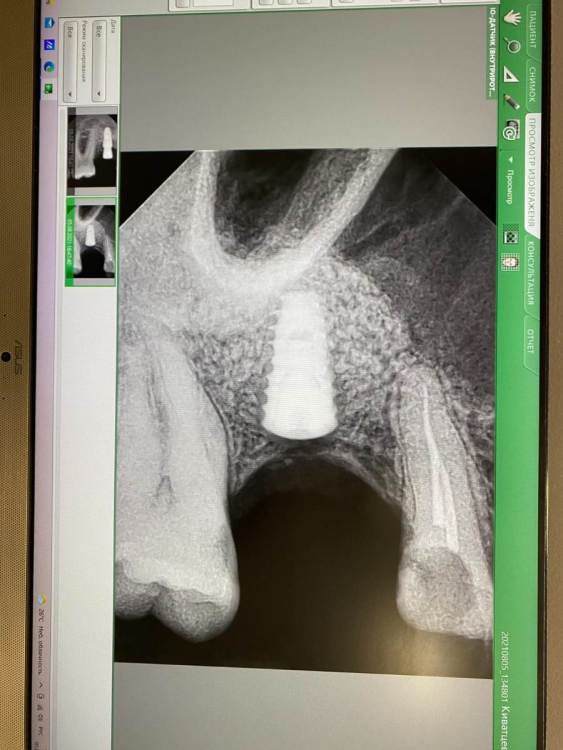

kamranchick Опубликовано 5 августа, 2021 Поделиться Опубликовано 5 августа, 2021 Приветствую, первый раз сталкиваюсь с подобной ситуаций стандартная ситуация, ОСЛ с использованием чистого апатос кортикал, ожидание 5 месяцев,заживление без осложнений сегодня начинаю сверление, и один сплошной фиброз какой прогноз коллеги? стоит ждать чуда? прилагаю снимки Ссылка на комментарий

syrovovec Опубликовано 15 октября, 2021 Поделиться Опубликовано 15 октября, 2021 6 лет пользовался апатосом в синусах, за последний год в 3 ОСЛ выгреб не измененный графт. Перешел на Мр 3 в синус Ссылка на комментарий

kamranchick Опубликовано 15 октября, 2021 Автор Поделиться Опубликовано 15 октября, 2021 mp3 усадку дает нехилую) какая интересно есть хорошая альтернатива остебиолу, кроме байоссса интересно Ссылка на комментарий

pit Опубликовано 16 октября, 2021 Поделиться Опубликовано 16 октября, 2021 05.08.2021 в 18:09, kamranchick сказал: Приветствую, первый раз сталкиваюсь с подобной ситуаций стандартная ситуация, ОСЛ с использованием чистого апатос кортикал, ожидание 5 месяцев,заживление без осложнений сегодня начинаю сверление, и один сплошной фиброз какой прогноз коллеги? стоит ждать чуда? прилагаю снимки Коллаген содержащий апатос был? Ссылка на комментарий

kamranchick Опубликовано 16 октября, 2021 Автор Поделиться Опубликовано 16 октября, 2021 проблема в основном на кортикале... не миксе Ссылка на комментарий